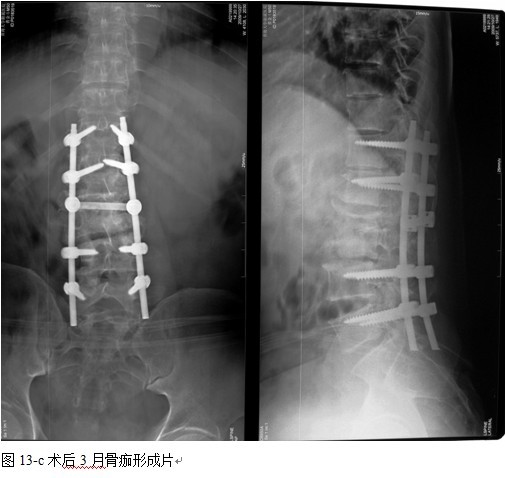

结果: 术后所有患者均显示,骨性融合, 马尾神经损伤的患者均基本恢复正常,术后后凸畸形平均矫正90%以上, 3-49个月的随访,后凸角度平均丢失4.2°。

本组手术用时间3~4h , 平均3.5h 。术中出血300~500ml , 平均约350ml 。术后症状完全缓解,无神经功能障碍加重等并发症,1例营养差的老年患者伤口出现窦道,1例因肝功能差,术后未口服抗痨药,伤口出现窦道,经换药后二期愈合,其余病例伤口均一期愈合。马尾神经受损的患者术后基本恢复正常。术后一周后凸角平均 5.4°后凸畸形平均矫正90%以上, 最终后凸角平均8.3°,后凸角度平均丢失4.2°。随访3个月有87%(40/46)有骨痂形成,6个月91.3%(42/46)明显骨性愈合(见图),其余4例9-12个月内愈合,随访时间3-32个月,平均11个月,46例患者中2例在术后2个月和3个月时背部形成脓肿,换药后治愈。2例出院1月后并发结核性脑膜炎,治疗后好转。1例因椎弓根钉偏外,刺激神经根,5个月后从侧方脱出,疼痛加重,因前后路植骨完全愈合,取出后症状完全缓解。